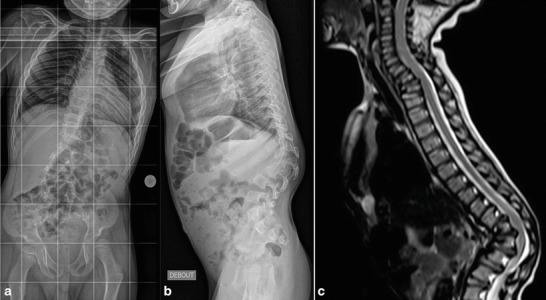

Fig. 1.

Preopertive radiograph (a) and MRI (b and c) of patient 1. T12 apical thoracolumbar kyphosis of 40° in prone position, (a) reduced to 22° when in supine position. 45° T2 craniocervical kyphosis unchanged when in supine position (a and b)